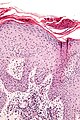

Microscopic

Micro

The sections show a raised lesion with compact hyperkeratosis and irregular acanthosis. Spongiosis is seen focally. There is minimal hypergranulosis.

There is no thinning of the suprapapillary plate and no dilated superficial blood vessels. There is no interface activity.